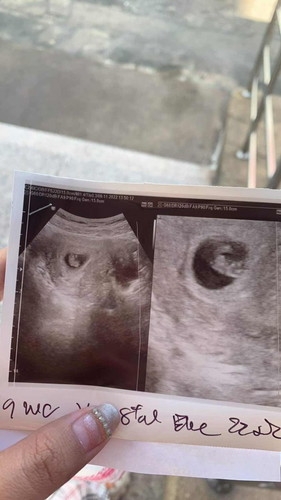

9 weeks ตัวเท่านี้ปกติมั้ยคะแม่ๆ#ขอบคุณสำหรับคำตอบค่ะ #ท้องแรกคะ #คุณแม่ๆช่วยแนะนำหน่อยค่ะ

วันนี้เพิ่งไปซาวด์มา นับเอง 8w 6 day แต่เครื่องบอก 8w3day ขนาด 1.89 cm. ค่ะ

บ้านนี้ซาวตอน 8w5d น้อง 2.09cmค่ะ ไม่รู้ว่าเท่านี้ปกติไหม

เราซาวด์ตอน 8วีค 4 วัน น้อง 2cm ค่ะ

บ้านนี้ 8week 1.85 เซนครับ

บ้านนี้8w 1.57เซนเอง

บ้านนี้ 9w 2.35 cm. ค่ะ

ซาว 9w5D น้อง 3.01 cm คะ

บ้านนี้ 11W 4cm. คะ